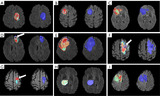

project image

Hemodynamic property incorporated brain tumor segmentation by deep learning and density-based analysis of dynamic susceptibility contrast-enhanced magnetic resonance imaging (MRI)

Leonardo Tang, Tianhe Wu, Ranliang Hu, Quanquan Gu, Xiaofeng Yang, Hui Mao

Quantitative Imaging in Medicine and Surgery, 2024

bib / paper

Magnetic resonance imaging (MRI) is a primary non-invasive imaging modality for tumor segmentation, leveraging its exceptional soft tissue contrast and high resolution. Current segmentation methods typically focus on structural MRI, such as T1-weighted post-contrast-enhanced or fluid-attenuated inversion recovery (FLAIR) sequences. However, these methods overlook the blood perfusion and hemodynamic properties of tumors, readily derived from dynamic susceptibility contrast (DSC) enhanced MRI. This study introduces a novel hybrid method combining density-based analysis of hemodynamic properties in time-dependent perfusion imaging with deep learning spatial segmentation techniques to enhance tumor segmentation.